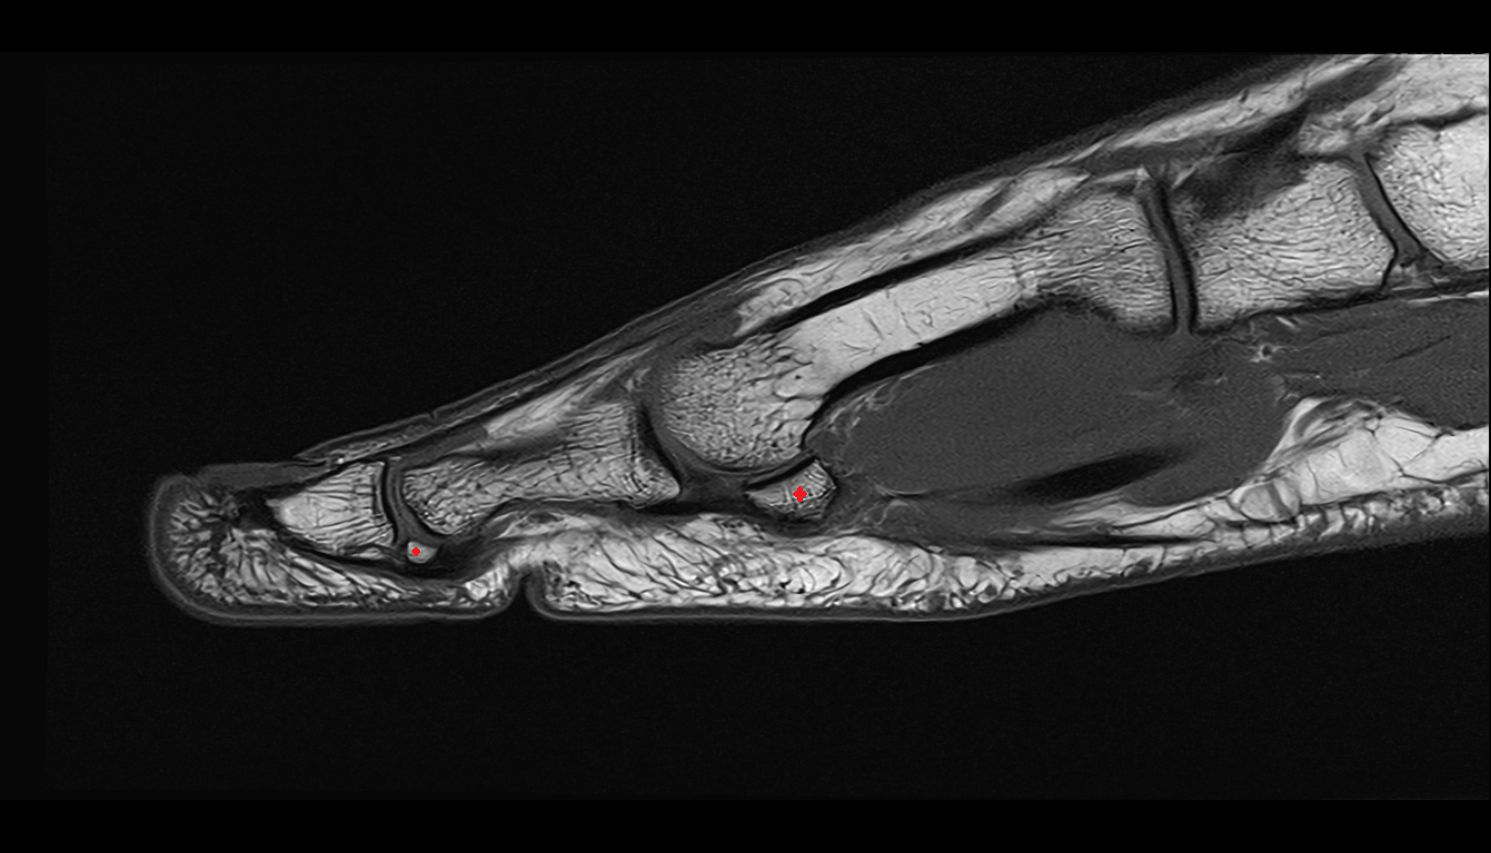

- Sesamoid bone of great toe

- Lateral sesamoid bone

- Medial sesamoid bone